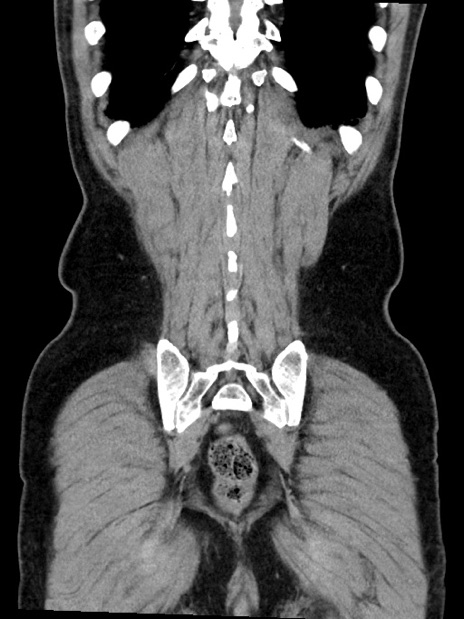

症例35(冠状断像)

【症例】70歳代 男性

【主訴】腹部膨満、嘔吐

【現病歴】昨日より腹部膨満感出現。本日増悪し、仙痛出現。嘔吐あり、受診。

【既往歴】糖尿病、胆摘後

【身体所見】BP 149/80mmHg、HR 74/min、BT 35.9℃、腹部:膨満、軟、圧痛なし。腸雑音減弱あり。上腹部正中切開瘢痕あり。

【データ】WBC 13500、CRP 1.72